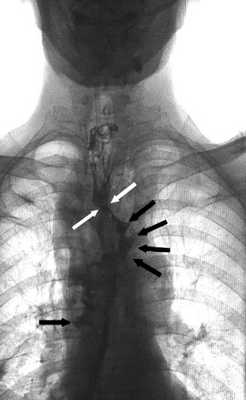

Все манипуляции проводили после тщательного обследования пациента с целью уточнения расположения, размера дефекта анастомоза, а также выявления затеков в средостение, плевральную или брюшную полости. Несостоятельность анастомоза диагностировали при рентгенологическом исследовании верхних отделов желудочно-кишечного тракта с использованием водорастворимого контрастного препарата (рис. 1). Рис. 1. Рентгенограмма верхних отделов желудочно-кишечного тракта с водорастворимым контрастом у пациента после трансхиатальной эзофагэктомии с пластикой пищевода изоперистальтической желудочной трубкой. Желтыми стрелками указана зона несостоятельности анастомоза, красными — область затека контрастного препарата.